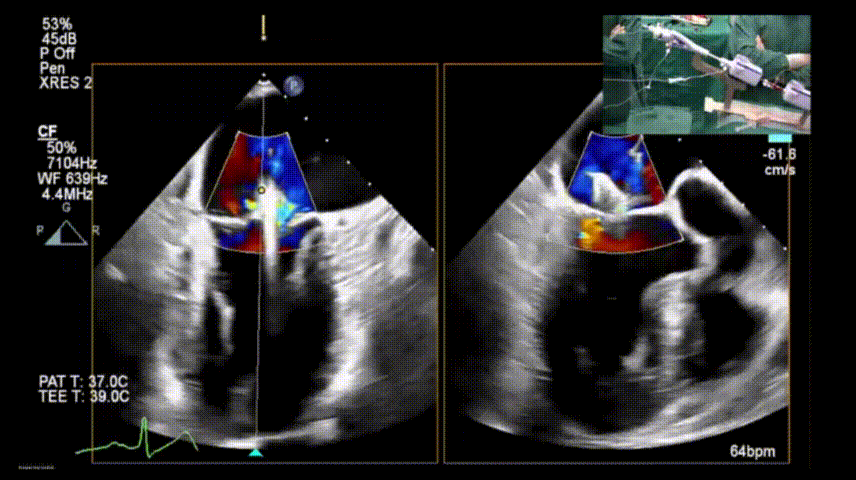

X-plane视图下完成夹子释放

彩色多普勒显示夹子位于A2-P2区,少量残余反流

图片

二尖瓣口平均跨瓣压差:2mmHg